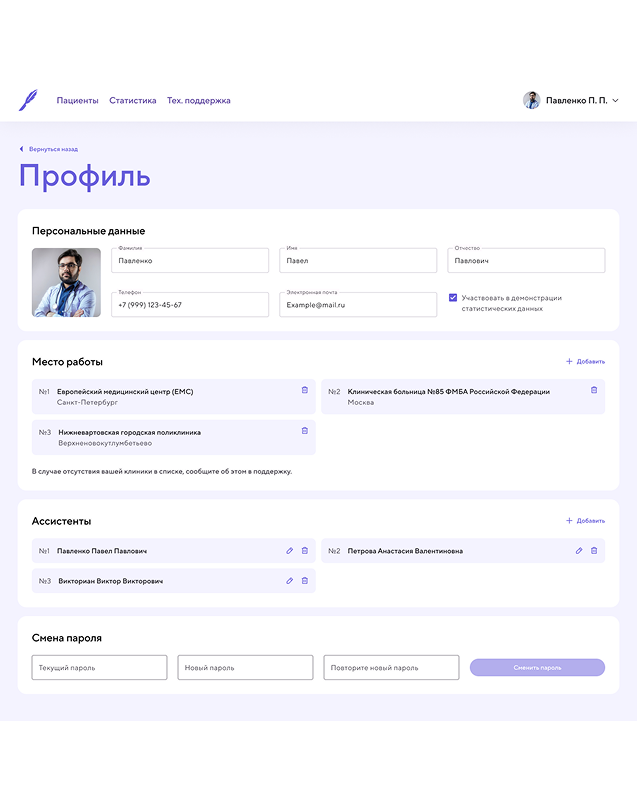

CRM Приложение [ 2022 ]

Работал над CRM-приложением для хирургической клиники по снижению лишнего веса, разработанным с использованием Pug, Vanilla.js и CSS. Приложение предназначено для ведения и учета пациентов, управления операциями и отслеживания результатов лечения.

В рамках проекта реализованы: авторизация и роли пользователей, создание и ведение карт пациентов, продвинутая фильтрация по различным параметрам, а также большие формы для создания операций и наблюдения за пациентами. Для визуализации результатов лечения использовались Chart.js, позволяя наглядно отображать статистику и эффективность применяемых методов.

Я работал над архитектурой интерфейса, реализацией ключевых функций, обеспечением удобного и логичного взаимодействия с данными, а также над оптимизацией форм и графиков для комфортной работы медицинского персонала. Приложение получилось функциональным, наглядным и удобным инструментом для управления пациентами и анализа результатов клиники.

Завершен

Velgir

Вернуться к списку проектов